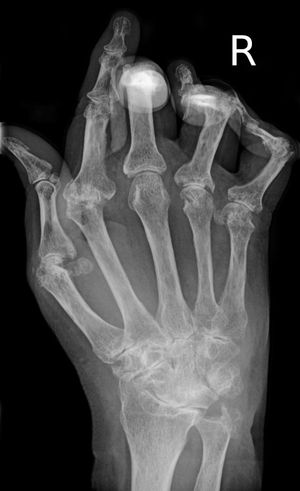

류마티스 관절염 환자의 손 X선 사진

• 영상 검사: X선, 자기공명영상(MRI), 초음파 등을 통해 관절의 염증 및 손상 정도를 확인한다.[20][73] 고주파 트랜스듀서(10MHz 이상)를 이용한 초음파 검사는 기존의 방사선 사진보다 20% 더 많은 골 손상을 보여준다.[74] 컬러 도플러 및 파워 도플러 초음파는 활막 염증의 정도를 평가하는 데 유용하다.[74]